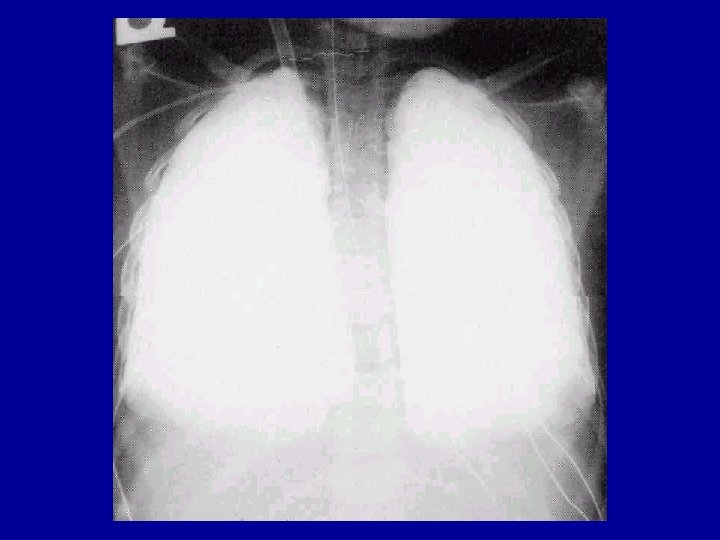

Left Lung Pneumonia with Effusion

ARDS (Bilateral Infiltrates)